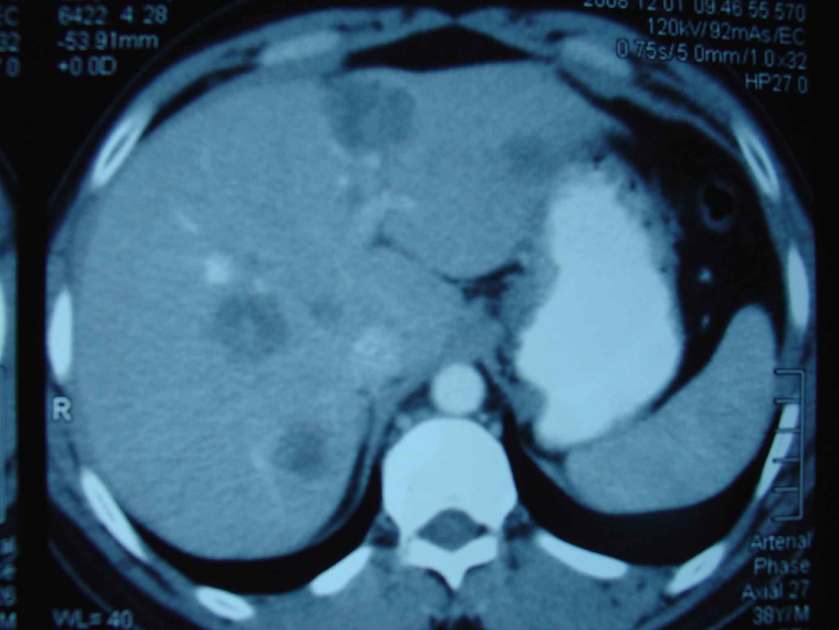

Ram is a 38-year-old male. He had stomach pains for about 3 months. His stools were hard and sometimes were blood stained. He went to a private hospital and did an X-ray. The doctor found nothing wrong with him. But his problems still persisted. Ram went to another private hospital. A CTscan on 17 April 2007 showed a 3.5 cm mass at the recto-sigmoid junction. There were multiple nodules approximately 10 mm each in Segments 6 and 8 of the liver. These represent liver metastases.

However, his illness did not go away. Blood test result on 1 December 2008 showed CEA = 15.9 (high) while a CT scan on the same day showed:

1. multiple peripheral nodules in both lungs, predominantly the upper lobes. Conclusion: lung metastasis.

2. the liver is of normal size and shape but there are multiple enhancing lesion throughout.Conclusion: liver metastasis and paraaortic lymphadenopathy.